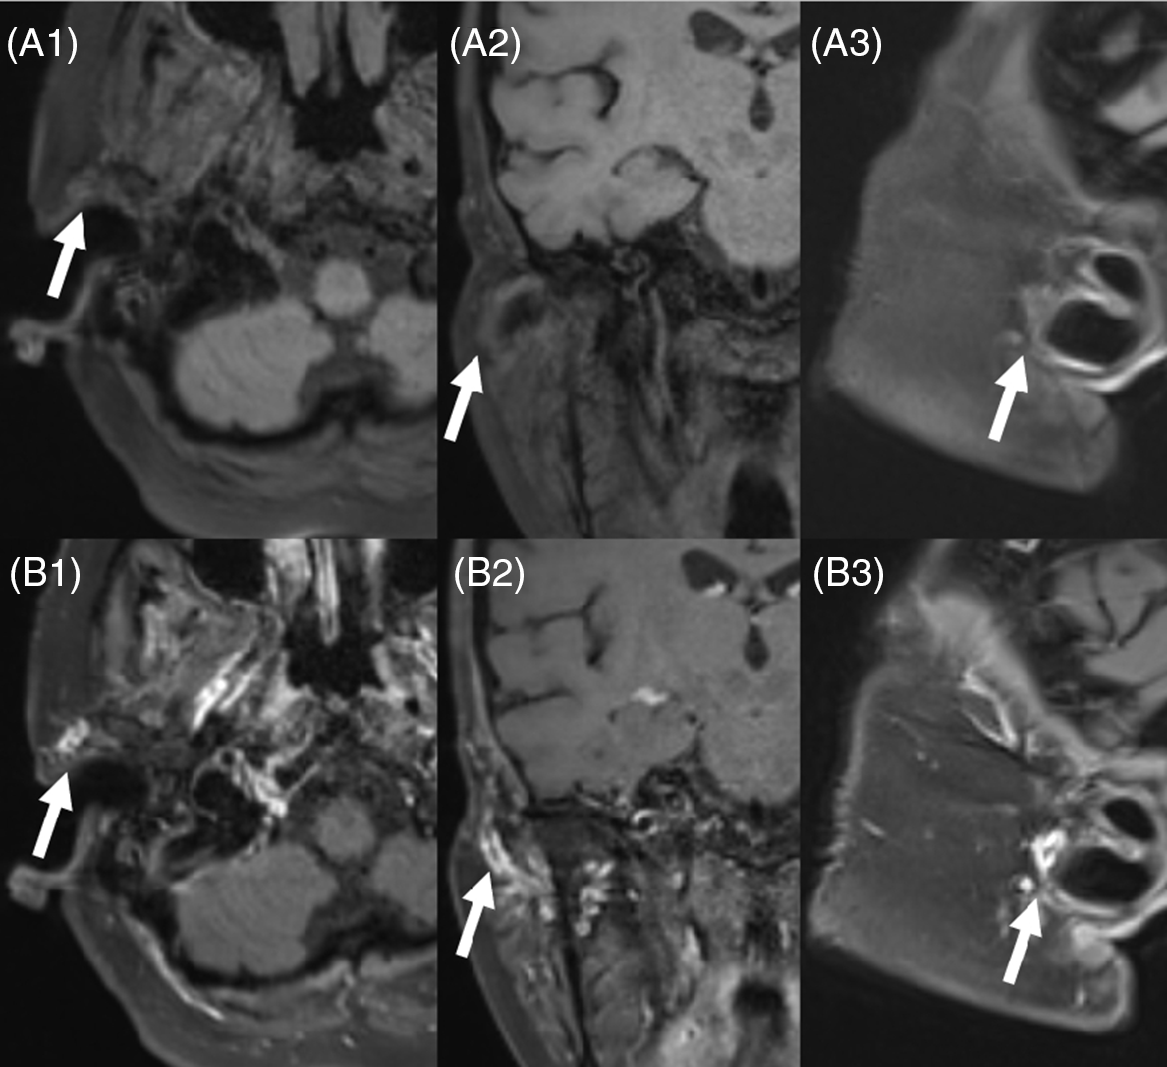

A 68-year-old female presents with recent onset of bilateral sequential no-light-perception vision secondary to presumed giant cell arteritis. The patient had markedly elevated CRP/ESR (CRP 51.2 mg/L (normal <1 mg/L) and ESR > 130 mm/hr (normal <30 mm/hr)). The patient received IV methylprednisolone. Neither temporal artery could be palpated. Only the preauricular portion of the right temporal artery had a faint pulse and a biopsy in this area was deemed unsafe due to the risk of facial nerve injury. Reference Shin, Shin, Lee, Koh and Song1 On ultrasound, the arteries were nonaudible. High-resolution scalp vessel wall magnetic resonance (MR) imaging at 3T was subsequently performed and demonstrated enhancement and thickening of the wall in the proximal segment of the right superficial temporal artery which was congruent with a diagnosis of giant cell arteritis. Immediate treatment with prednisone led to improvement of her constitutional symptoms; however, she had no significant recovery of vision. High-resolution scalp vessel wall MR imaging is a recently developed technique that has been applied to the diagnosis of giant cell arteritis. Reference Rheaume, Rebello and Pagnoux2,Reference Poillon, Collin and Benhamou3 Wall thickening and enhancement of the scalp arteries are key imaging features for the diagnosis of giant cell arteritis. Reference Rheaume, Rebello and Pagnoux2 Usage of 3D techniques rather than 2D techniques has also been shown to increase sensitivity. Reference Poillon, Collin and Benhamou3 Scalp vessel wall MR imaging can be helpful in cases precluded from temporal artery biopsy for the confirmation of diagnosis (Figure 1).

Figure 1: Pre- (A1–A3) and post- (B1–B3) contrast high-resolution MR 3D T1 FS Black Blood Images of the scalp vessels (in axial, coronal, and sagittal planes) demonstrate enhancement and thickening of the wall in the proximal segment of the right superficial temporal artery (arrow) in the region of palpable pulse.